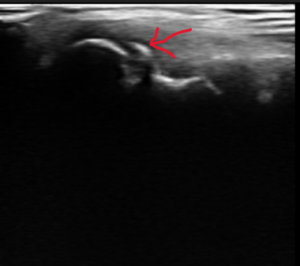

【野球肘 超音波~エコー~画像】

エコー画像では、上腕骨小頭という丸みのある骨(エコー画像 赤丸部)が正常な場合は、滑らかな半円を描きますが、野球肘側の画像はギザギザしているのが確認できます。